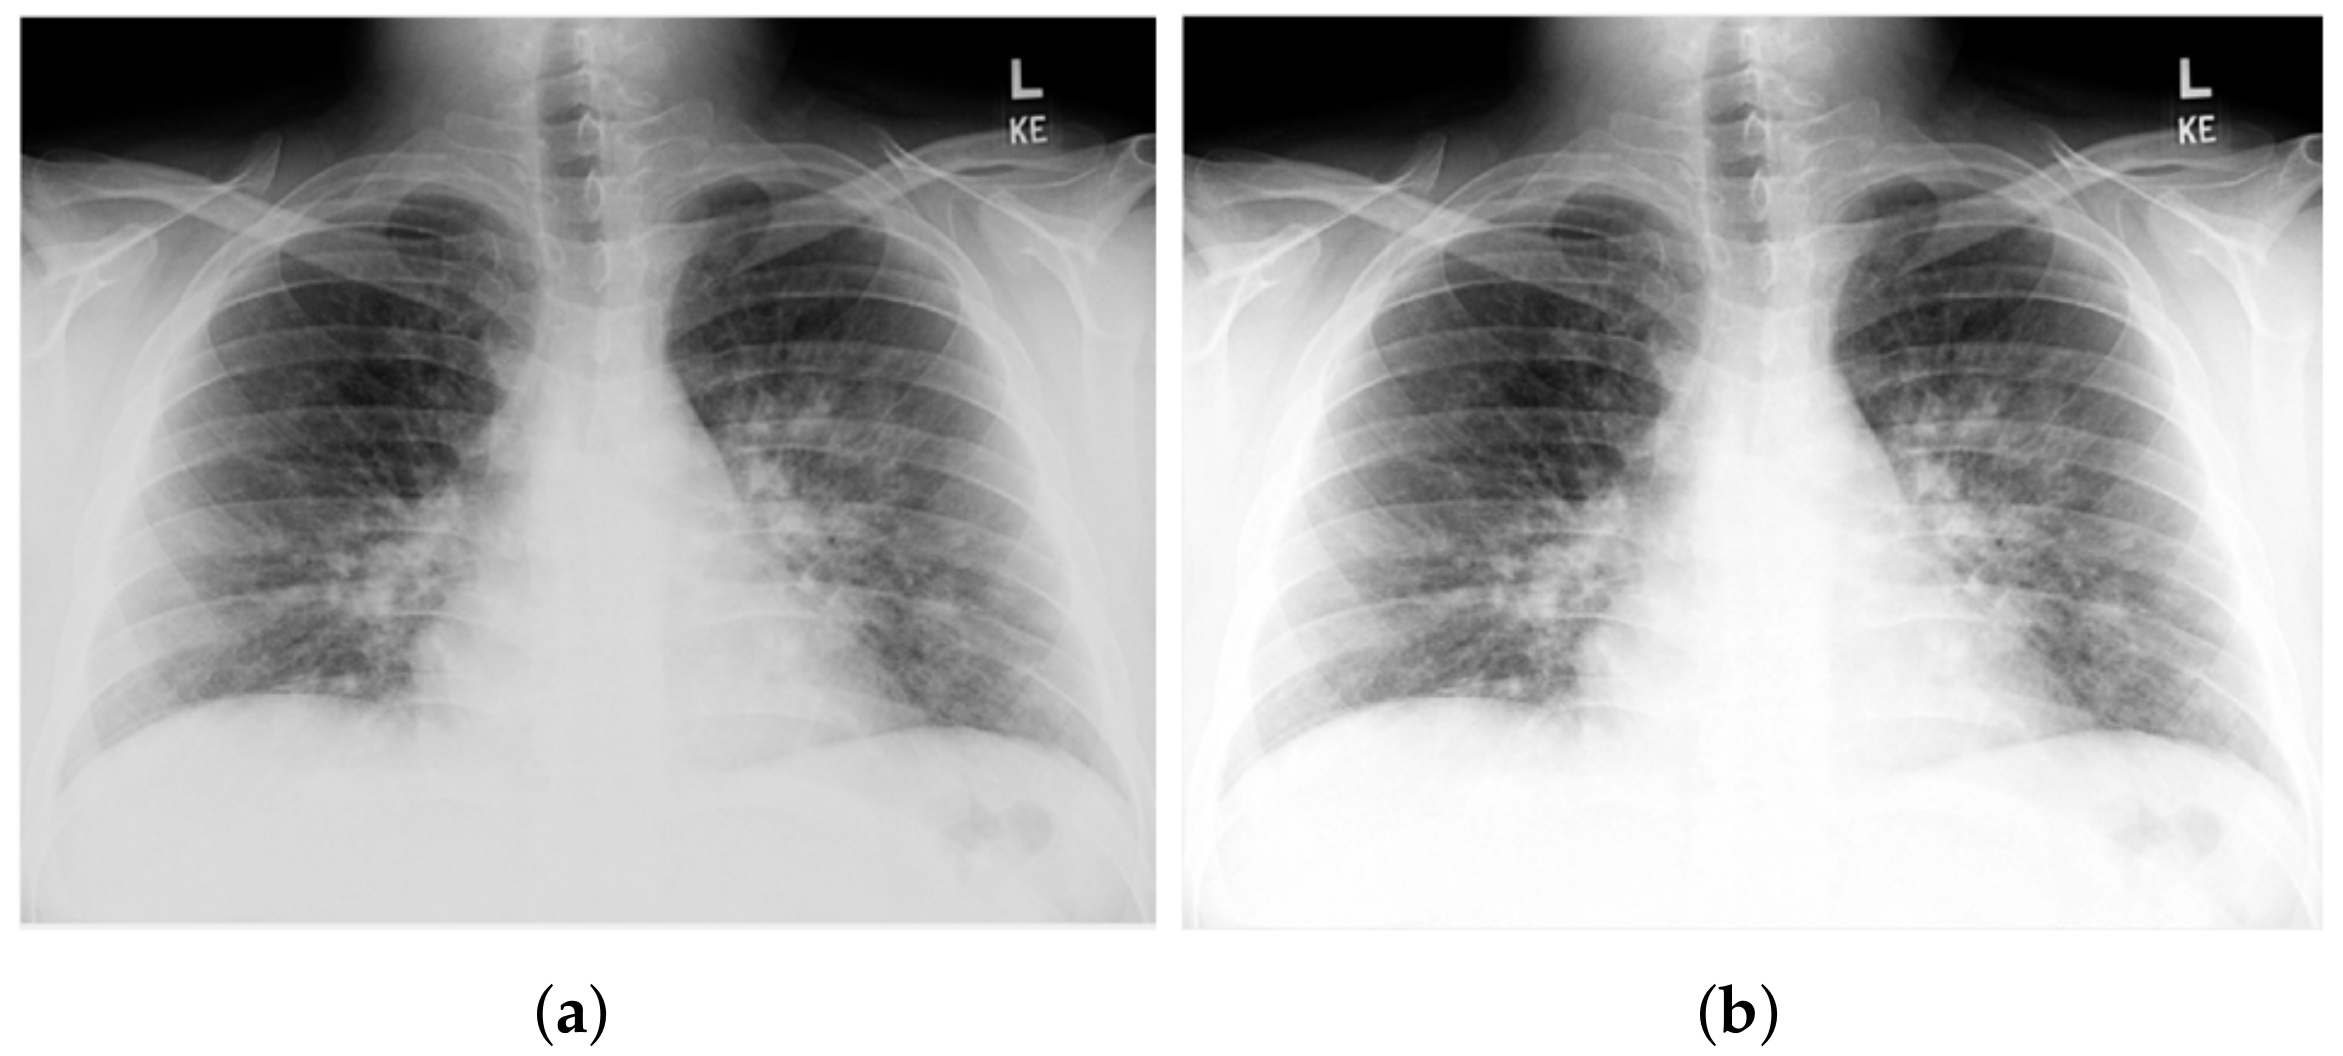

3.1. COV-PEN Image Datasets